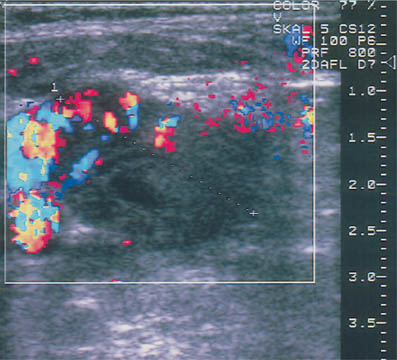

19 Doppler Ultrasound The vascularization of malignant tumors is a phenomenon well known from pathologic, biochemical, and angiographic studies, and we know that the degree of neovascularization correlates with the biologic behavior of the tumor. Thermography, once widely used as an adjunct to clinical examination, can detect the change in surface temperature associated with the focal increase in blood flow to a breast malignancy. However, it has been discredited as a screening method for breast cancer because of its low sensitivity, poor specificity (inflammatory processes as well as cancer are associated with local heat), and lack of precise anatomic localization (Williams et al., 1990). Contrast-enhanced MRI is also based on angiogenesis in malignant tumors as well as other factors such as membrane permeability. For many cancers, but certainly not all, there is an intense rapid rise followed by signal washout after the administration of a paramagnetic contrast agent, most commonly a gadolinium chelate such as gadopentate dimeglumine. The measurement of tumor blood flow is more applicable to lesion characterization than to screening. But there are anatomic situations that hamper evaluation of the breast tissue, and there are tumors that do not display typical diagnostic features, and the measurement of tissue blood flow can be helpful in evaluating problem cases of this kind. It should be understood, however, that the measurement of tumor blood flow is a nonspecific assessment that cannot differentiate lesions with absolute confidence. The degree of blood flow correlates with tissue metabolism. Thus, while fast-growing malignancies generally have a copious blood supply, blood flow is also increased in proliferative benign tumors, in pregnancy and lactation, and in inflammatory conditions. Doppler ultrasound has been used for more than 20 years to analyze blood flow in breast tumors. Initially only continuous-wave (CW) Doppler systems were available. These devices are very sensitive, but they require an experienced user and it is difficult to examine nonpalpable lesions. Pulsed Doppler systems became popular in the early 1980 s, as they allow for selective flow sampling in vessels that are located by ultrasound imaging. Tumor vessels are very small, however, and usually cannot be visualized in the B-mode image. It is tedious to move the Doppler sample volume through the image while searching the tumor and its surroundings for blood vessels. Also, most of the older duplex scanners used a low frequency and were relatively insensitive in detecting tumor vessels. As a result, duplex scanning did not find significant applications in tumor diagnosis. Color flow imaging paved the way for the use of Doppler ultra-sound in tumor diagnosis. The first instruments had poor sensitivity. By the 1990 s, however, color Doppler technology had advanced sufficiently to permit the effective localization of tumor vessels (Fig. 19.1). This was achieved through the use of higher Doppler frequencies and improved signal processing. The recording of Doppler spectra was also improved and provides additional information on tumor blood flow (Fig. 19.2). Nevertheless, color Doppler demonstrates only a portion of the vessels. This is due to the limited sensitivity of Doppler in detecting microscopically small vessels and the dependence of the Doppler principle on the beam–vessel angle. Vessels that are perpendicular to the beam direction are poorly detected. Blood flowing in the direction of the beam results in a higher frequency shift and a better recorded signal. Fig. 19.1 Color Doppler image of invasive ductal carcinoma. The greatest vascular density is found at the periphery of the tumor. Note the predominantly radial pattern of vessels converging on the tumor. The high sensitivity setting, with a PRF of 800 Hz, often leads to aliasing in the vessels due to the high flow velocities. This must be tolerated, since increasing the PRF would decrease Doppler sensitivity and reduce the number of detectable vessels. Fig. 19.2 Color Doppler and duplex sonography for the measurement of blood flow. Again, most vessels are found at the tumor periphery. The Doppler spectrum shows a high systolic blood flow velocity (37.9 cm/s) and an absence of flow in diastole (RI = 1.0). This high resistance pattern is typical of breast carcinoma. Breast carcinomas often have a firm consistency, exerting a pressure that collapses the blood vessels within the tumor. As a result, only peripheral vessels can be seen in most cases and the flow resistance is high. To improve the visualization of small vessels and avoid the problem of insonation angle, a different method of signal processing was developed. This technique, called power Doppler, does not register the angle-dependent frequency shift but the intensity (amplitude) of the reflected signals, which depends on volume flow. As a result, the course of tumor vessels is more clearly visualized (Fig. 19.3 a, b). This technique is susceptible to artifacts, however, and much experience is needed to interpret the images correctly. Another disadvantage is that, for the present, power Doppler imaging yields nonquantitative information. The image is interpreted subjectively, and there are no objective parameters that can be used for tumor differentiation. For these reasons, color Doppler is still preferred. It is easily combined with duplex technology for concomitant flow imaging and flowmetry. However, this requires a sensitive instrument with optimum settings. Given the range of variation among different instruments, standardization is difficult to achieve. In our previous studies at the University of Freiburg, we used the ATL UM9 HDI (Philips Medical Systems, Bothell, WA) color flow imager with a 10–5-MHz linear-array transducer. We used a 50–100 Hz filter and a pulse repetition frequency (PRF) of 800–1000 Hz. The power and gain were set as high as possible, that is, just below the noise level. Doppler ultrasound is used to investigate focal abnormalities rather than to scan the entire breast. Given the variability of tumor blood flow, all vessels should be sampled for the quantitation of flow. Because vessels often are not visualized within malignant tumors, particular attention should be given to feeding vessels that enter the periphery of the mass. With just enough pressure to maintain contact, the transducer should be placed lightly on the breast to avoid vascular compression. Before any vessels are sampled, various insonation angles should be tested to obtain an optimum Doppler signal. First a slow scan through the tumor is done in the color Doppler mode so that all the vessels can be located and counted. Then the examination is completed by analyzing flow signals in the duplex mode. Usually the course of the vessels can be seen, and so the probe angle can be adjusted to ensure an accurate measurement of flow velocity. Duplex analysis should include the determination of maximum systolic velocity (S) and end-diastolic velocity (D). This provides information on total blood flow and makes it possible to calculate indices from the Doppler spectra. The most important index to be determined is usually the resistance index (RI) or the AB ratio: RI = (S – D)/S AB ratio =S/D The pulsatility index (PI) is less frequently determined because it requires fitting an envelope curve to the Doppler spectrum. This is time-consuming and fraught with potential errors. Our comparative measurements have shown, moreover, that this index correlates closely with the RI and the AB ratio. Flow velocity analysis provides a basis for various calculations. For example, the vessel with the highest-velocity flow can be used for tumor differentiation. It is also possible to calculate the mean value for all the flow velocities measured in a particular tumor. Because carcinomas are supplied by many small, low-flow vessels in addition to a few large vessels, the mean velocity may be low despite a high total blood flow. A better way to assess total blood flow is to add together all the flow velocities measured in the tumor. It would be simpler and more accurate to use a computer to extract the total blood flow from the color Doppler data. Fig. 19.3 a, b Color Doppler and power Doppler images of a solid cellular carcinoma. The relatively soft consistency of this tumor accounts for the central vascular density. a Branching vessels can be identified in the color Doppler image. b The course of the vessel is seen somewhat more clearly in the power Doppler image, but individual vascular branches are not defined. Malignant tumors are associated with an increased number of blood vessels (Fig. 19.1, Table 19.1), which converge on the tumor and enter it in a radial pattern. Often, however, only vessels at the tumor periphery are visualized while vessels inside the tumor are collapsed as a result of the very firm consistency of most carcinomas. Although the vessels in malignancies often communicate through shunts and do not have a muscular coat, the hard tumor consistency leads to a high flow resistance (Fig. 19.2). Even so, the flow velocities in most tumor vessels are increased but are highly variable. The same applies to the Doppler spectra that are sampled from the vessels.